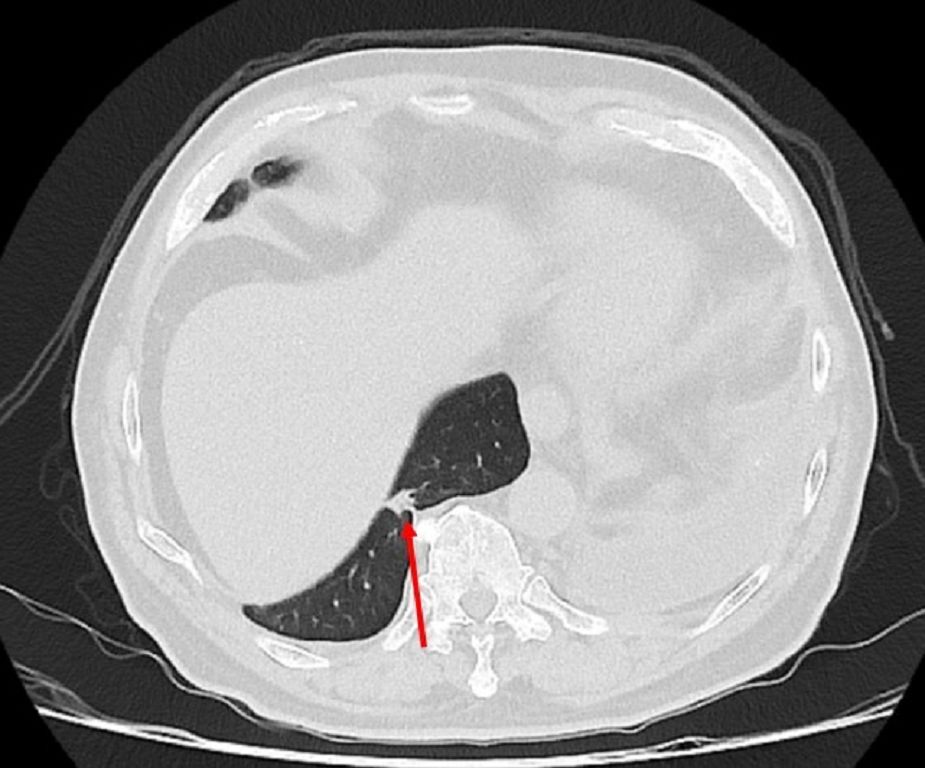

75歲吳先生因肝臟細胞癌在仁愛長庚合作聯盟醫院(大里仁愛醫院)接受治療,期間發現右下肺有一顆約1.2公分新發現的腫瘤,因疑似肺癌故轉介到胸腔及心臟血管外科廖啟耀主任門診,經醫療團隊和家屬討論後決定做手術切除該腫瘤。由於病人過去有車禍導致橫隔膜受傷的病史,所以讓手術預期難度相對提高,經採用達文西機器人手術系統執行肺節切除手術,並且順利地於術後第三天出院返家休養。

廖啟耀主任指出,仁愛與長庚醫療體系聯盟醫院近年來積極引進達文西機器人手術系統,並成立微創暨達文西手術中心,致力推動高品質、低侵襲性的手術照護。手術中病人的橫隔膜如果符合預期和肺臟沾黏,因此手術空間也較為狹小,達文西機器人手術可提供穩定的操作及清晰的手術視野,這對於外科醫師在分沾黏上是如虎添翼。達文西手術在這方面優勢更顯得突出,透過穩定且精細的操作,團隊將吳先生的橫隔膜與肺臟分離,並完成之後的肺節切除手術。

雖然因為外傷病史使手術困難度上升,廖啟耀主任的團隊藉由達文西機器人手臂幫助下成功完成手術,過往使用傳統開胸手術或胸腔鏡手術於類似的病人,常因為分沾黏導致肺破損所以需要較長的恢復時間,但是在進行達文西手術的過程中,不只術中沒有發生因為分沾黏常見的出血、肺破損等問題,吳先生在術後第二天便可拔除胸腔引流管,恢復順利。